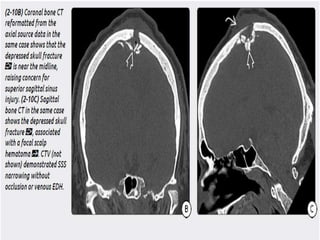

b) Depressed Skull Fractures- Depressed skull

fractures typically tear the underlying dura and

arachnoid and are associated with cortical

contusions and potential leakage of CSF into

the subdural space. Fractures extending to a

dural sinus or the jugular bulb are associated

with venous sinus thrombosis in 40% of cases.

Axial bone CT in a

patient who was hit in the

head with a falling ladder

shows an extensively

comminuted, depressed skull fracture.